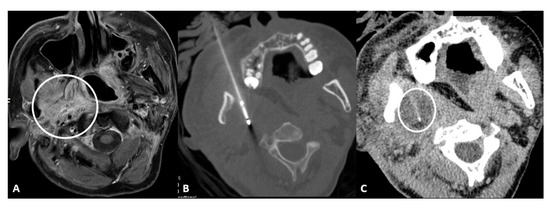

- Retromolar trigone: This is the space between the last molar and the mandibular condyle. It is a space without many vessels/nerves or vital structures; therefore, it represents a safe approach to treating pharyngeal and laryngeal lesions. Tongue positioning is mandatory, as it can flop backward against the ablation site resulting in frost injury: Forceps and a laryngoscope should be used to displace the tongue with gauze away from the ablation site to avoid this occurrence. In the case of tumors near the carotid artery, the patient can manifest severe hypotension and bradycardia during ablation. The presence of coils or metallic devices in a previously embolized carotid artery leads both to a loss of the cold-sink effect as well as a stimulation of the vagus nerve with thermal conduction down the carotid body (leading to the diving reflex). Cessation of cryoablation usually leads to spontaneous resolution (Figure 2).